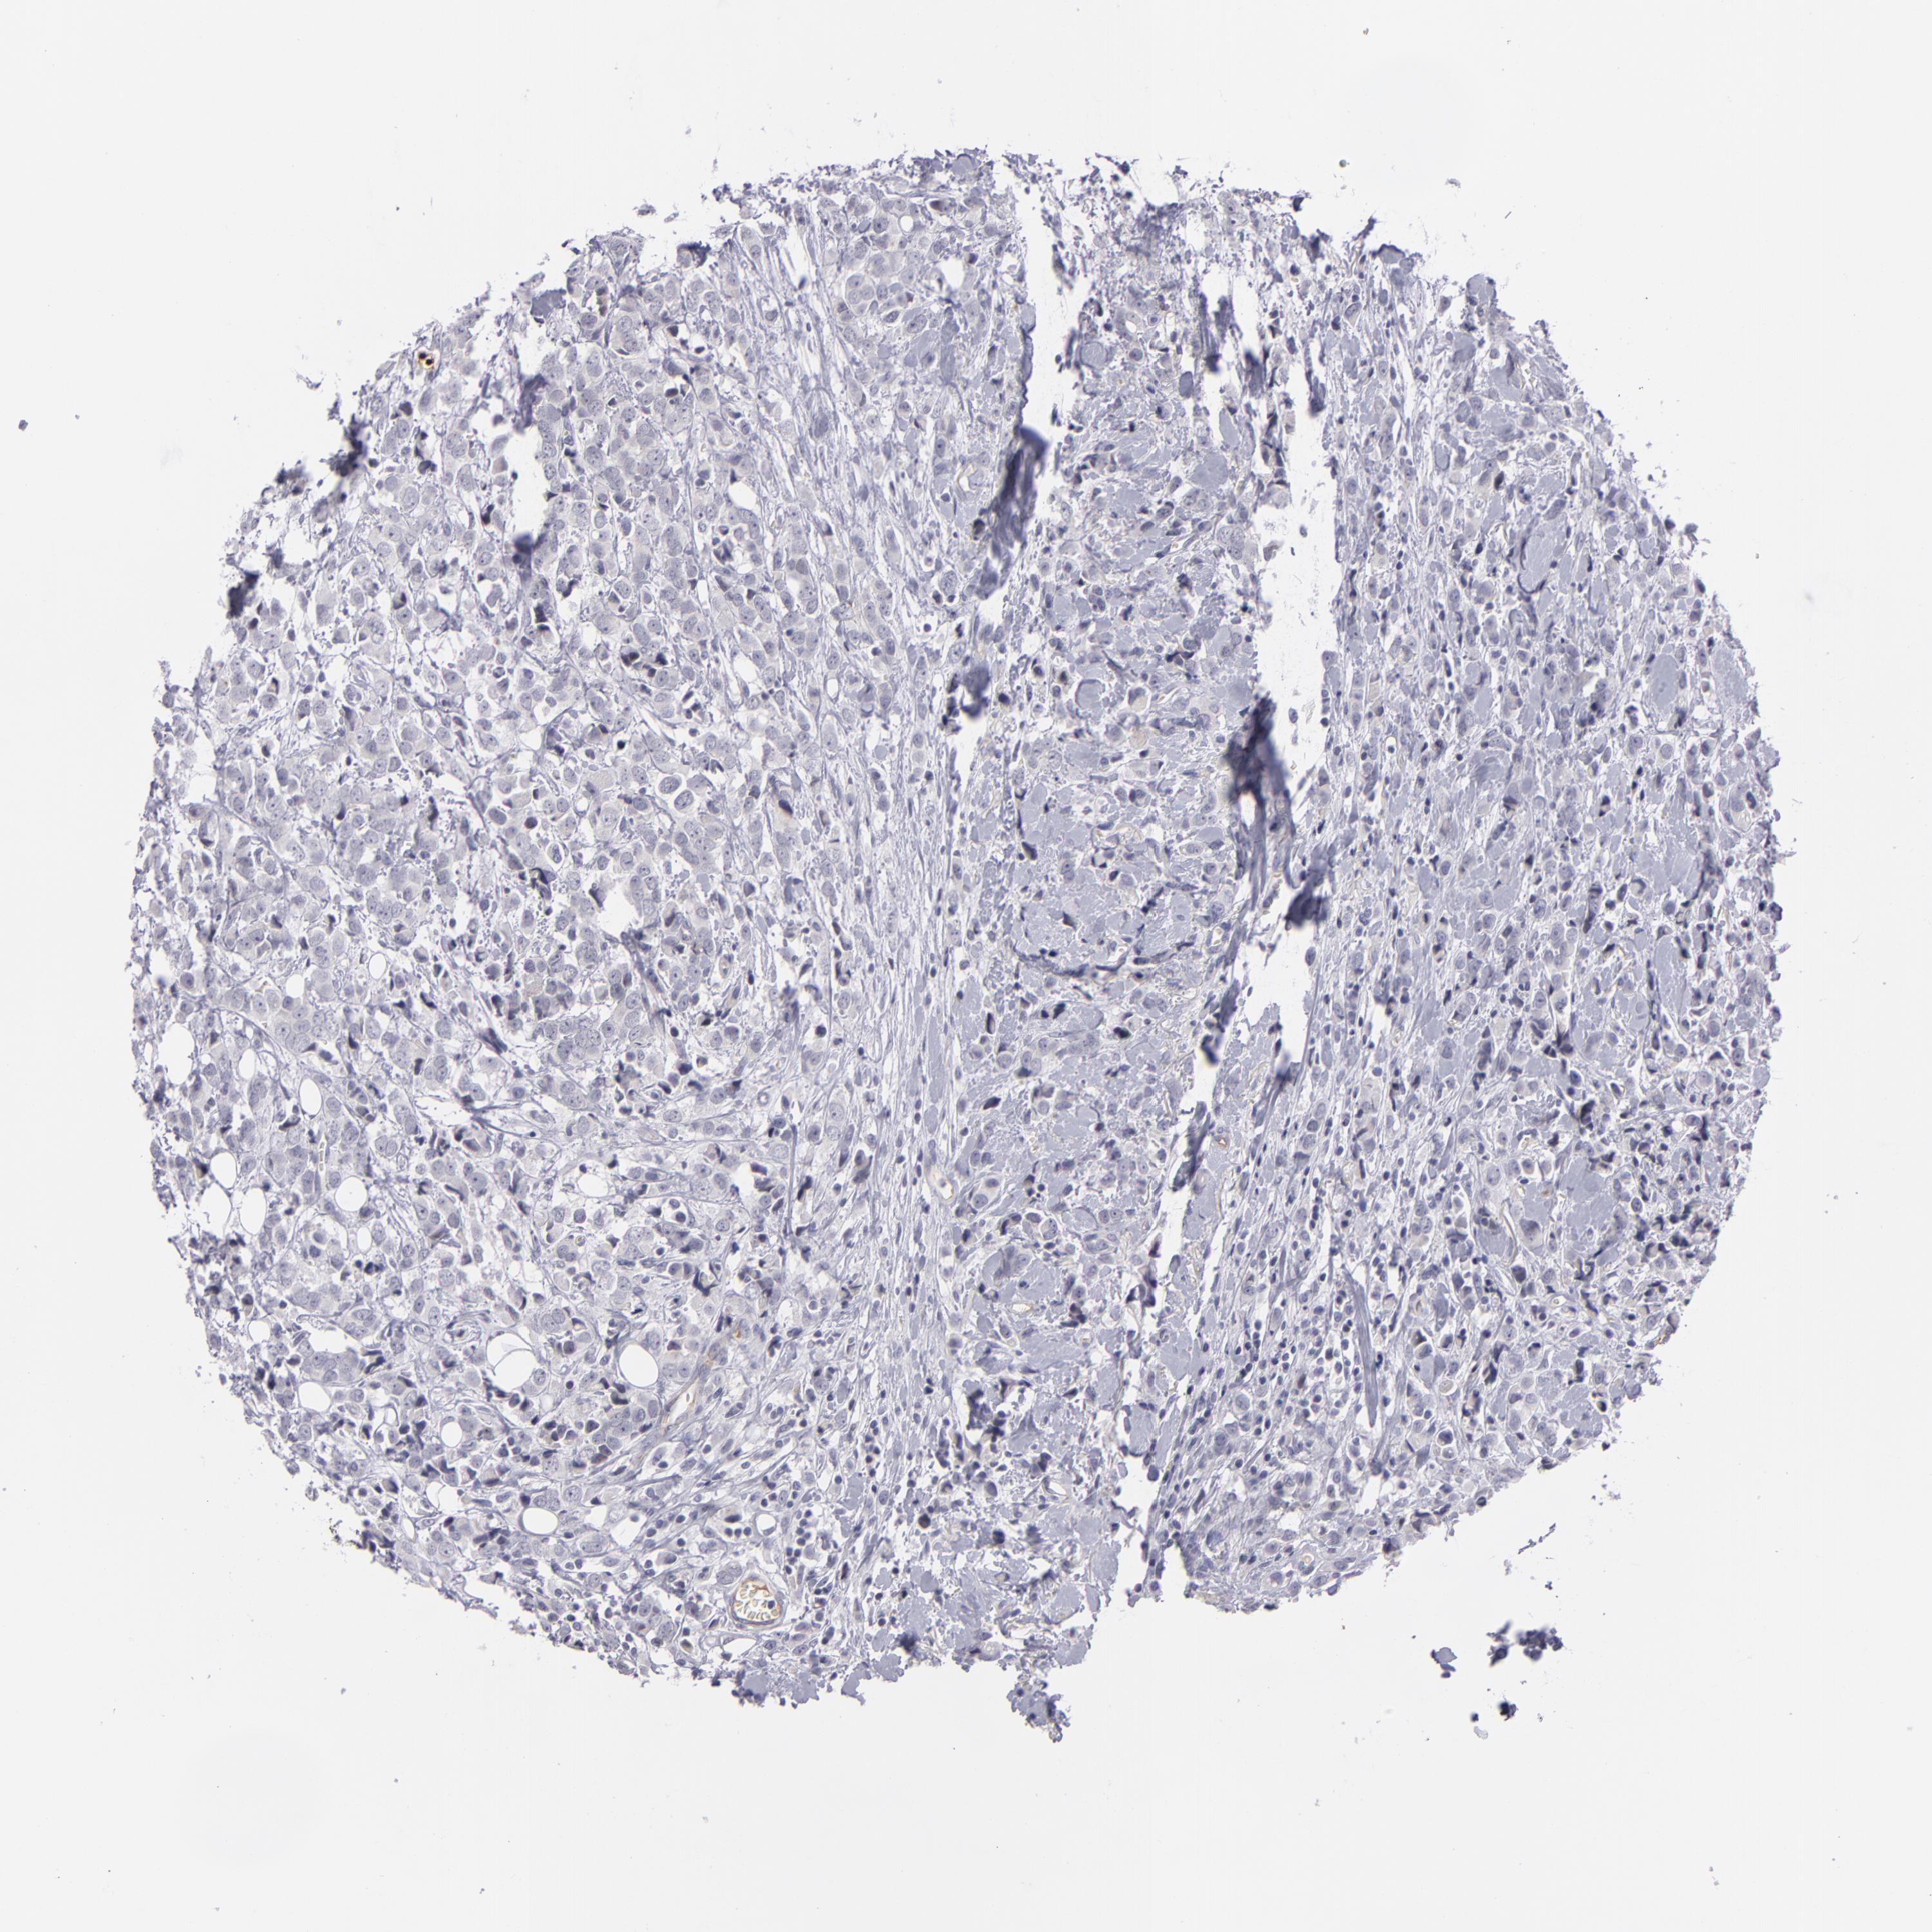

BRCA TCGA BRCA VALIDATION PROTEIN EXPRESSION